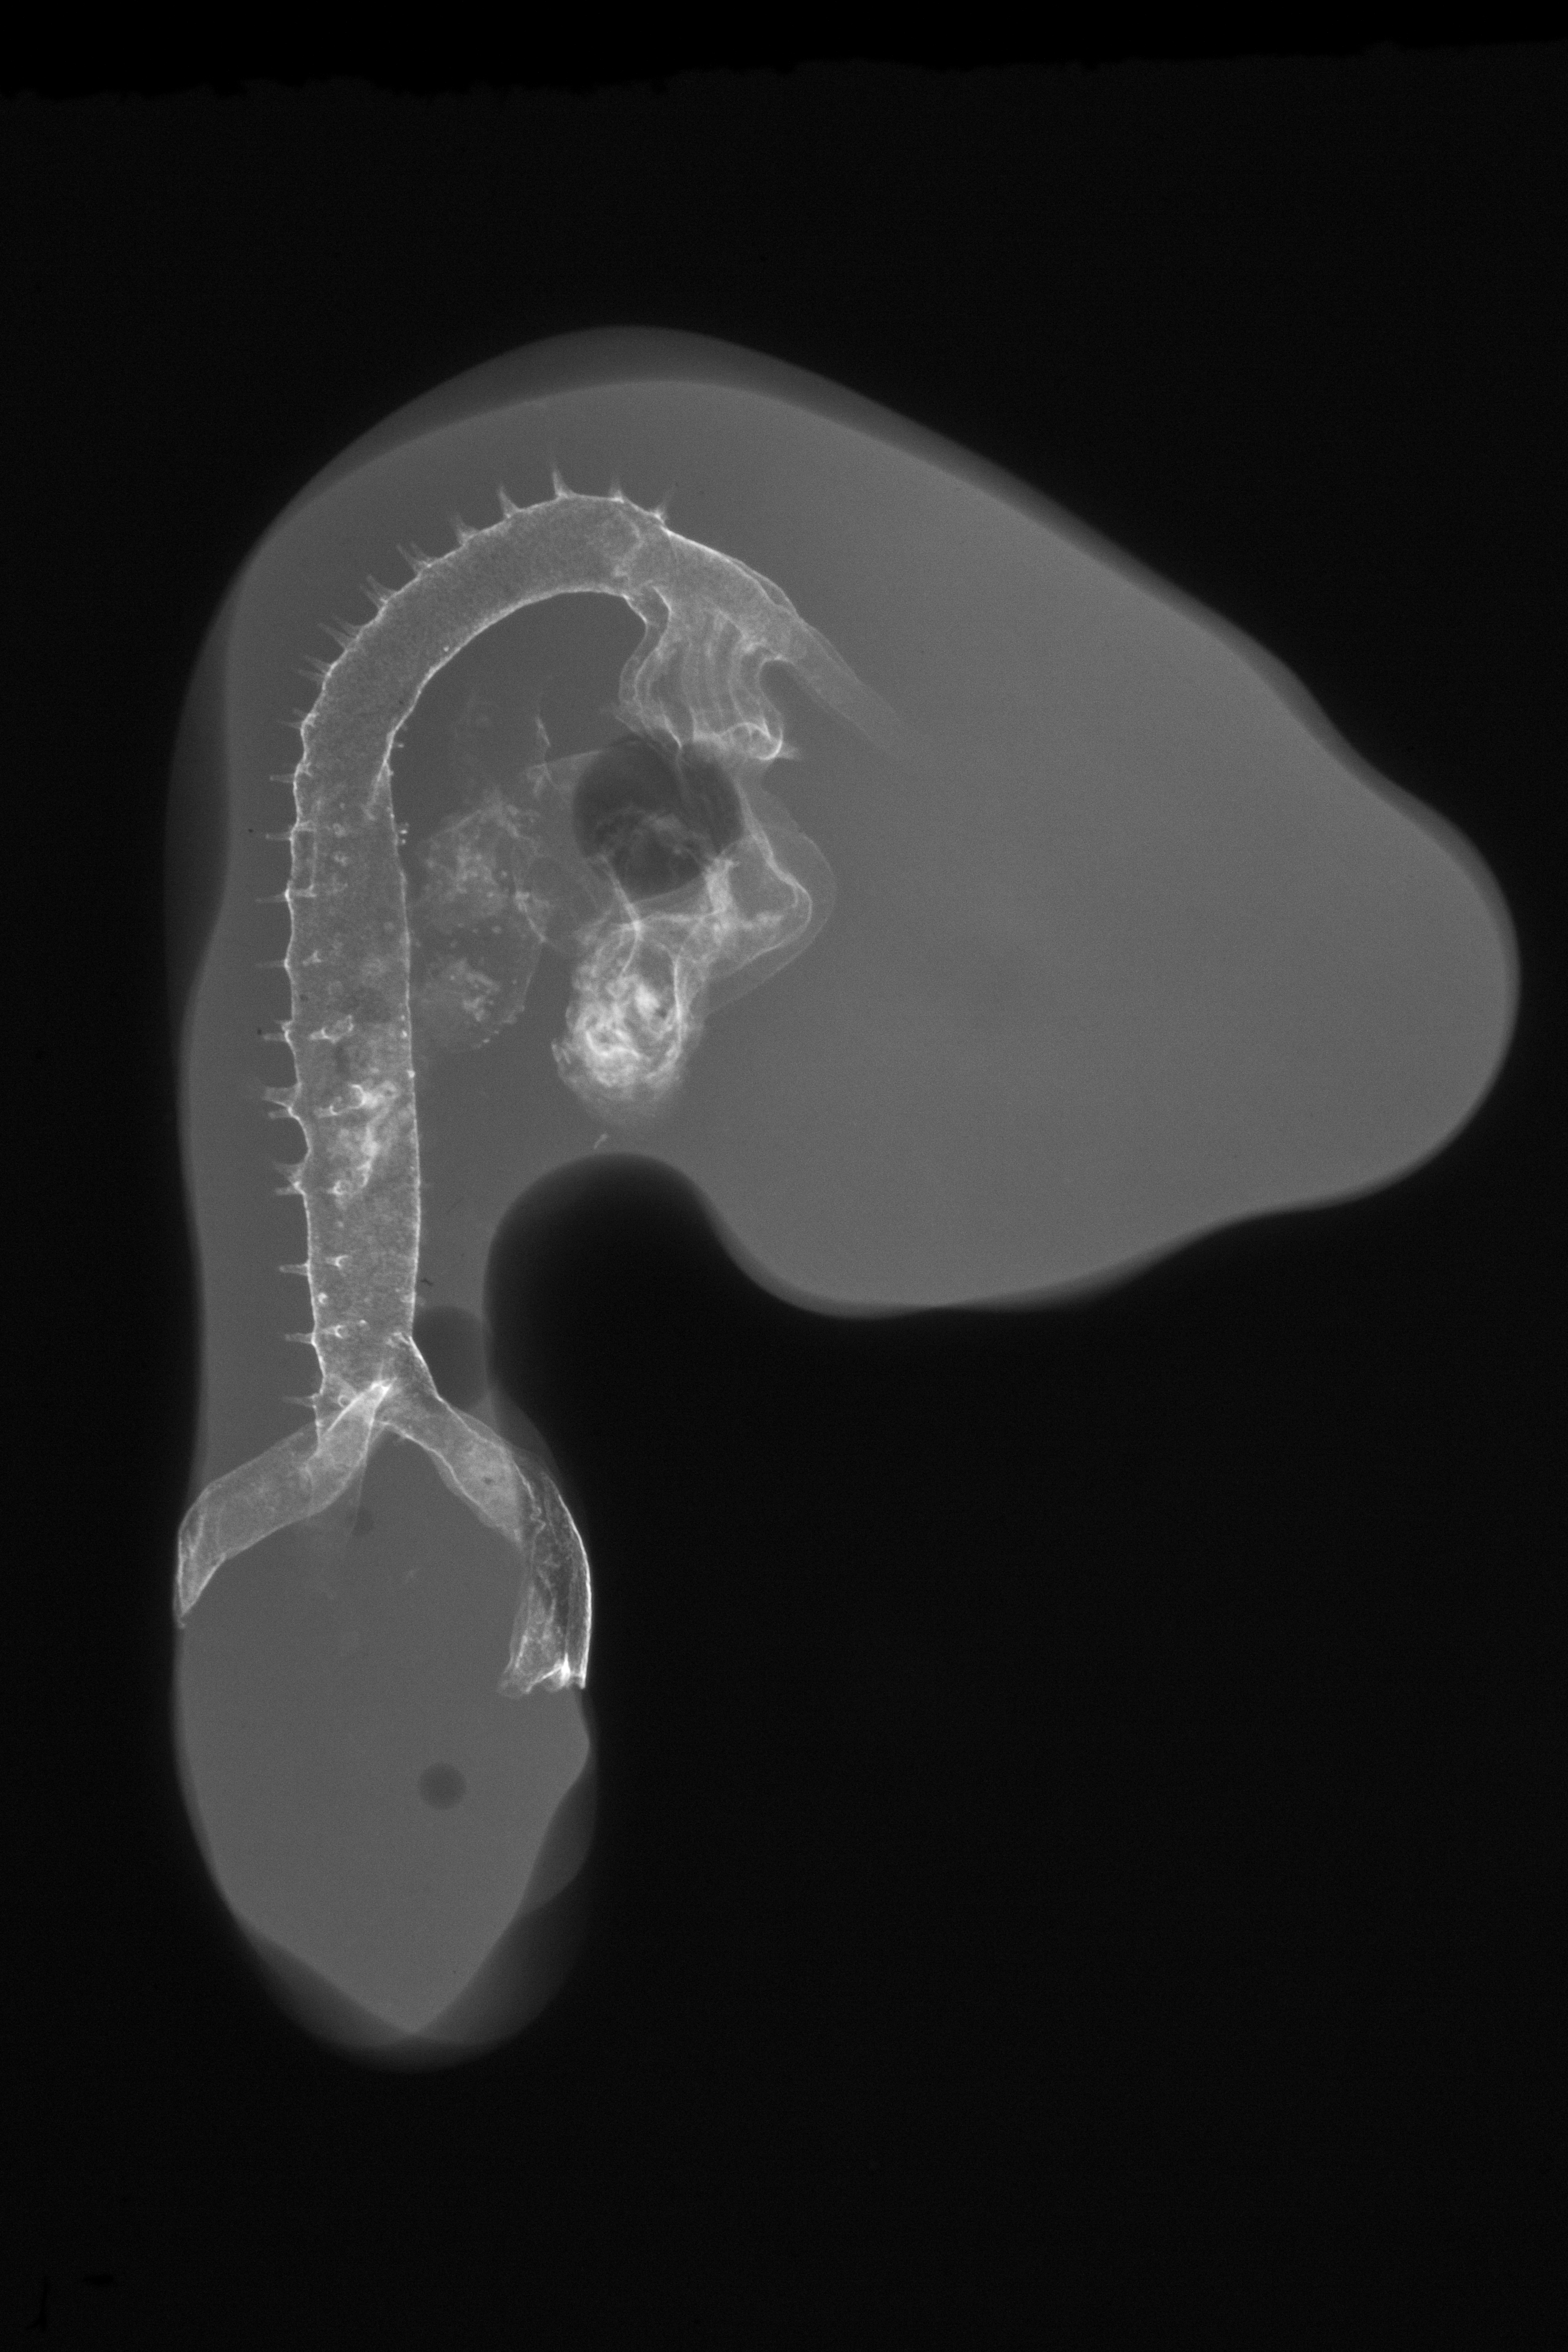

Chick Embryo Microangiography

Hamburger-Hamilton (HH) Stage 21 (approx. 3.5 days)

X-Ray Micrographs